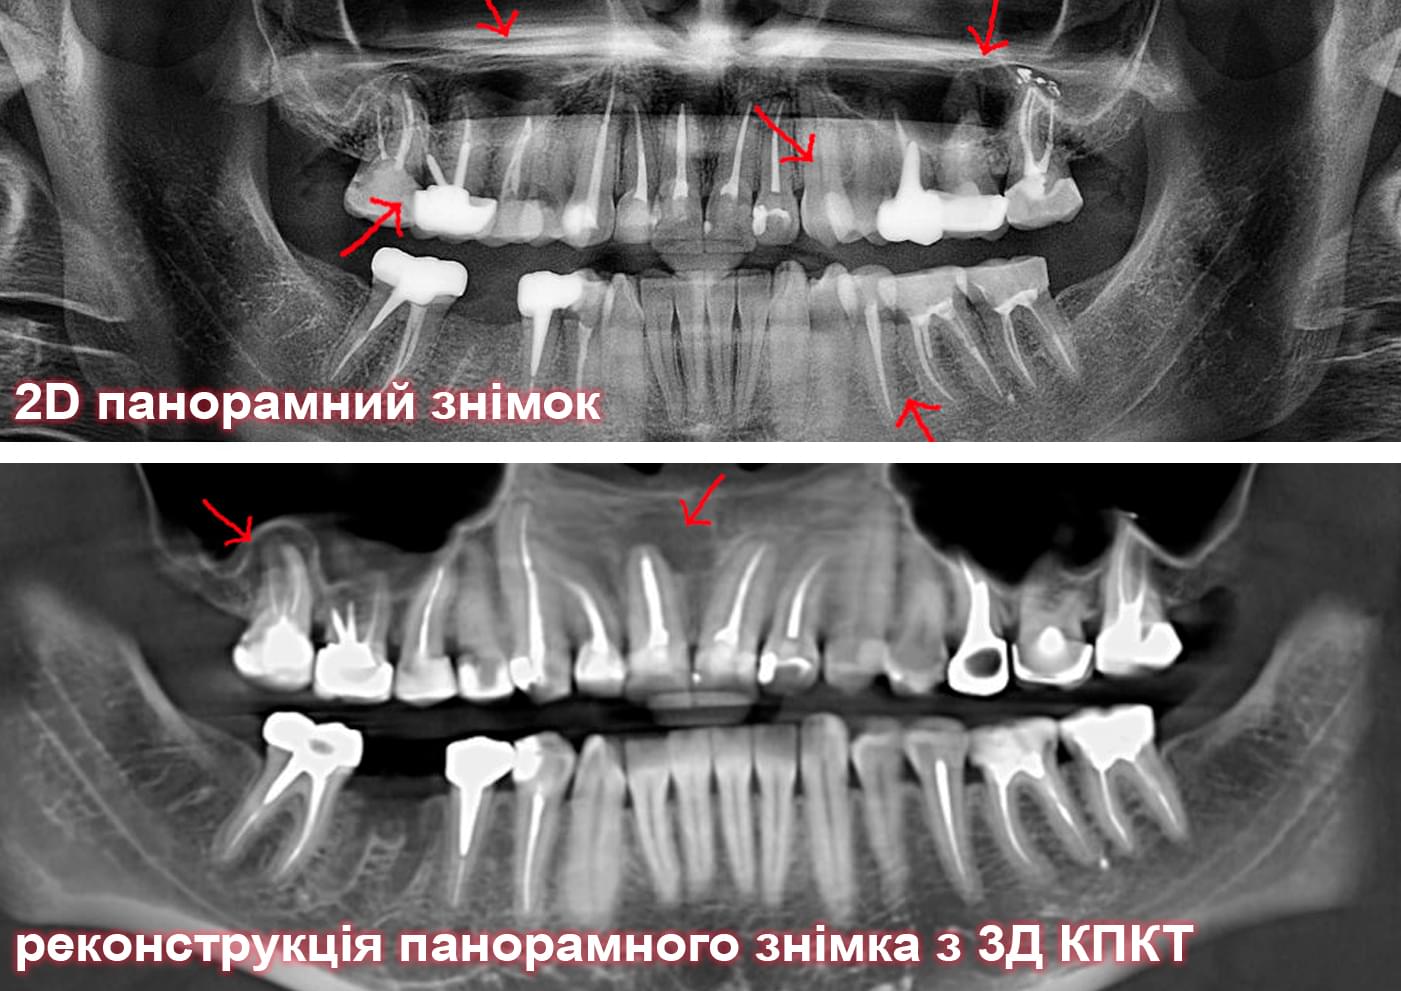

Головний недолік 2D-рентгену — це площинне зображення. Зуби, корені, щільна кістка та гайморові пазухи накладаються один на одного, створюючи «візуальний шум».

Візуальне порівняння (Кейс одного пацієнта)

Зуб — це не просто монолітний об'єкт, а складна система мікроканалів. На плоскому 2D-знімку вони часто перекривають один одного, створюючи ілюзію простої анатомії.